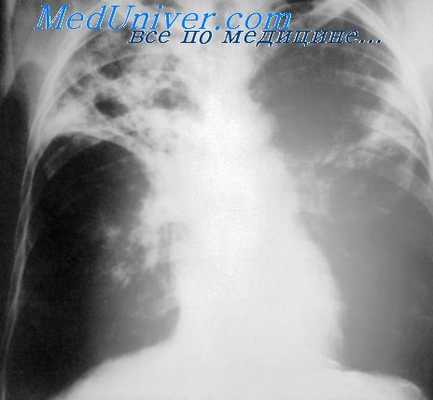

Комплексное исследование функции внешнего дыхания выявило хроническую дыхательную недостаточность у 148 из 154 больных (I ст. у 36, II ст.—50 и III ст.—у 62), что свидетельствовало о тяжести функциональных расстройств. В ближайшем послеоперационном периоде острая дыхательная недостаточность отмечена у 30 больных (19,5%), но только у 9 больных (5,9%) она была первичной, связанной непосредственно с нарушениями дооперационного периода и оперативным вмешательством.

По нашим данным хроническая дыхательная недостаточность не является абсолютным противопоказанием к выполнению пульмонэктомии по витальным показаниям. В подавляющем большинстве случаев удаляется нефункционирующий орган, что доказано нами по данным раздельной бронхоспирометрии, ангиопульмонографии, электрокимографии и изучением препаратов удаленных легких. Удаление основного источника инфекции и интоксикации, как показали наши наблюдения, способствует улучшению компенсаторных возможностей дыхания.